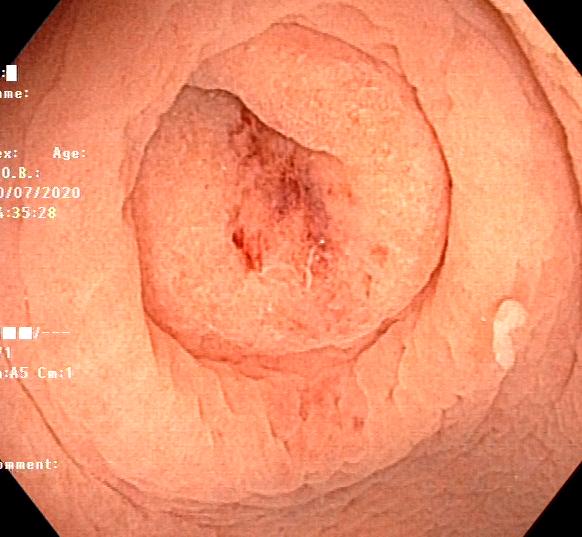

阑尾内口

水下再观察一下干干净净的阑尾开口是不是很nice!

然后循腔进镜到了阑尾开口,看到了阑尾开口有很多的脓液,因为不少患者饮食不规律,特别是在日本生活节奏快、压力大,特别是有受到打击时,小肠里有很多应激性溃疡,因此就进入了末端回肠,在里面给他注入了温水后,大家可以清晰的看到小肠的绒毛,以及多发的应激性小溃疡是非常清晰的。

在内镜前端透明帽的帮助下,推开Gerlach's瓣(黄箭头),并进行阑尾腔插管。当黄斑马导丝及导管置入阑尾腔时,可见脓性分泌物涌出。